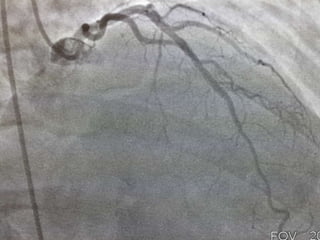

CASO CLINICO # 3

MASCULINO 65 AÑOS DE EDAD

DIABETES TIPO 2 DESDE HACE 15 AÑOS POBRE CONTROL METABOLICO

DISLIPIDEMIA. OBESIDAD GRADO II.

CUADRO CLINICO: ANGINA DE PECHO ATIPICA. CHEQUEO DE RUTINA. ECG DE

REPOSO NORMAL. PRUEBA DE ESFUERZO POSITIVA Y PRECOZ PARA ISQUEMIA.

TA 120/ 68 mm Hg. FC 67/min Fr 13/ min

Glucosa en Ayunas 215 mg /dL. Colesterol total 260 mg/dL, LDL 135 mg d/L

Creatinina 1.2 mg/dL

EXAMEN FISICO ANODINO

CASO CLINICO #3 MASCULINO 65 AÑOS DE EDAD DIABETES TIPO 2 DESDE HACE 15 AÑOS POBRE CONTROL METABOLICO DISLIPIDEMIA. OBESIDAD GRADO II. CUADRO CLINICO: ANGINA DE PECHO ATIPICA. CHEQUEO DE RUTINA. ECG DE REPOSO NORMAL. PRUEBA DE ESFUERZO POSITIVA Y PRECOZ PARA ISQUEMIA. TA 120/ 68 mm Hg. FC 67/min Fr 13/ min Glucosa en Ayunas 215 mg /dL. Colesterol total 260 mg/dL, LDL 135 mg d/L Creatinina 1.2 mg/dL EXAMEN FISICO ANODINO